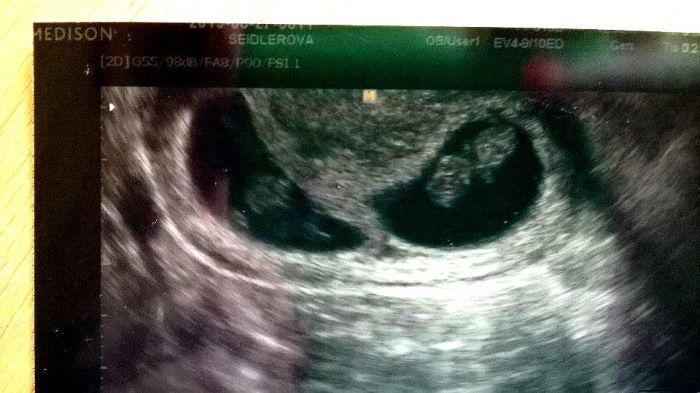

Ahoj holky moje! Tak konečně jsem dorazila domů, a hned Vám jdu napsat info.

Obě dvě miminka se jeví dobře, máme 20 mm....a odpovídáme cca tomu 8tt+5 ...

Holky, ty miminka dělaly uplné kotrmelce

Mudr. je nemohla změřit, nepovedla se jí ani fotečka, jedno miminko nejde moc vidět, protože se pořád vrtělo, prostě to lépe nešlo

Jinak, mám prý zvětšenou dělohu krásně, jak kdybych končila 10.tt a přitom ŽÁDNÉ PŘÍZNAKY ani bolesti podbříšku. Mudr říkala, že nic takového nemusí být.... Holky, další kontrolu mám přesně za 14 dní i s odběrem krve na screening....